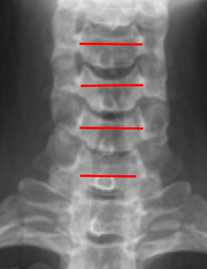

Image Type Cervical Spine X-Ray CT Scan MRI Scan Atlantodental Interval (ADI) Basion-Axial Interval Basion-Dens Interval (BDI) C2 Tilt C2–C7 Coronal Cobb Angle Cervical C2-7 lordosis C2-C7 Translation Chamberlain’s Line / McGregor’s Line Flexion-Extension George’s Line (Posterior Cervical Line) K-Line Interpedicular Distance (IPD) Occiput-C2 Angle Occipital Condyle–C1 Interval (CCI) Posterior Atlantodental Interval (PADI) Power’s ratio Sagittal Canal Diameter Sagittal Vertical Axis (SVA) Spinolaminar line Swischuk Line T1 Slope Torg/Pavlov Canal-to-Body Ratio